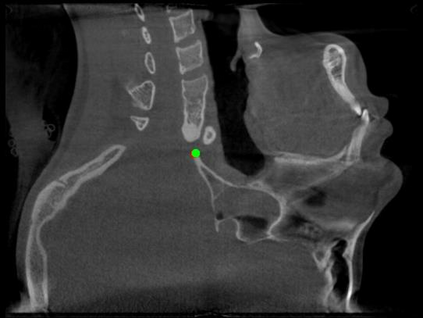

Detecting 3D landmarks on cone-beam computed tomography (CBCT) is crucial to assessing and quantifying the anatomical abnormalities in 3D cephalometric analysis. However, the current methods are time-consuming and suffer from large biases in landmark localization, leading to unreliable diagnosis results. In this work, we propose a novel Structure-Aware Long Short-Term Memory framework (SA-LSTM) for efficient and accurate 3D landmark detection. To reduce the computational burden, SA-LSTM is designed in two stages. It first locates the coarse landmarks via heatmap regression on a down-sampled CBCT volume and then progressively refines landmarks by attentive offset regression using multi-resolution cropped patches. To boost accuracy, SA-LSTM captures global-local dependence among the cropping patches via self-attention. Specifically, a novel graph attention module implicitly encodes the landmark's global structure to rationalize the predicted position. Moreover, a novel attention-gated module recursively filters irrelevant local features and maintains high-confident local predictions for aggregating the final result. Experiments conducted on an in-house dataset and a public dataset show that our method outperforms state-of-the-art methods, achieving 1.64 mm and 2.37 mm average errors, respectively. Furthermore, our method is very efficient, taking only 0.5 seconds for inferring the whole CBCT volume of resolution 768$\times$768$\times$576.